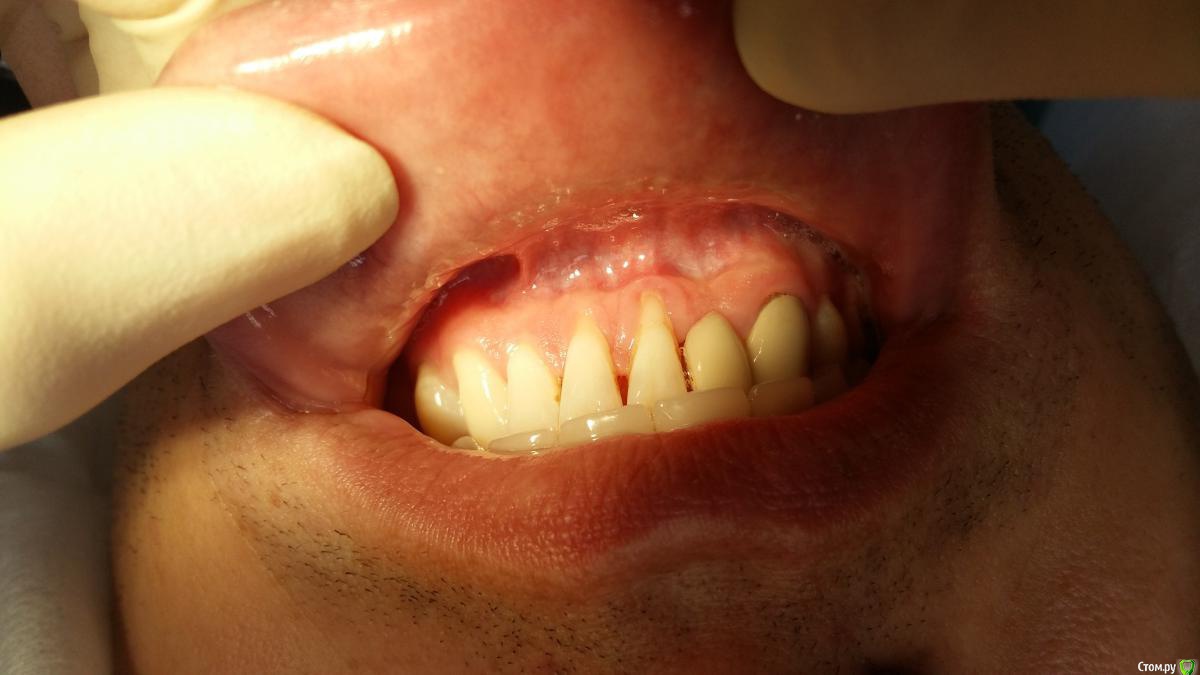

Zubnik7 Опубликовано 24 января, 2017 Автор Поделиться Опубликовано 24 января, 2017 Результат ч/з 3 недели после снятия швов.Был откинут лоскут,коронально смещен,под него в обл 41,31 фиксирован субэпит.трансплантат.стоит ли еще увеличивать зону ЗКПД? Ссылка на комментарий

Zubnik7 Опубликовано 24 января, 2017 Автор Поделиться Опубликовано 24 января, 2017 До операции и после в одном фото Ссылка на комментарий